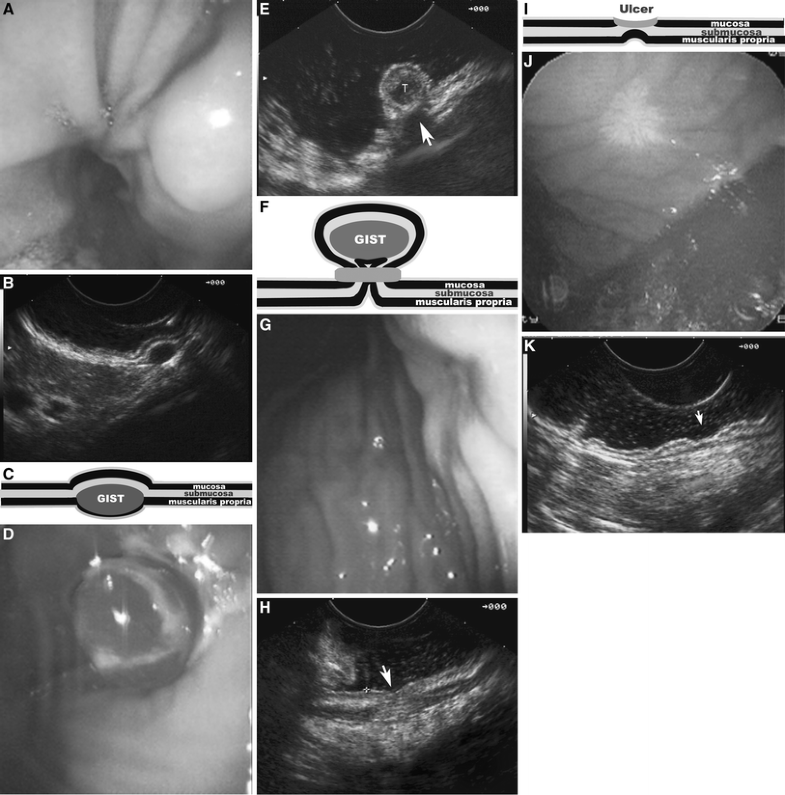

Dr. Arvind Trindade Endoscopic Resection What Is Endoscopic Banding It works by capturing the varix within a small band, resulting in occlusion. Endoscopic variceal banding (also called ligation). Endoscopic variceal ligation, or endoscopic band ligation, is a procedure that uses elastic bands to treat enlarged veins, or varices, in your. That's the tube that carries. The two forms of endoscopic therapy are: Your doctor used a lighted tube (endoscope,. What Is Endoscopic Banding.

Management of small subepithelial tumors by endoscopic banding without What Is Endoscopic Banding It works by capturing the varix within a small band, resulting in occlusion. Endoscopic variceal ligation, or endoscopic band ligation, is a procedure that uses elastic bands to treat enlarged veins, or varices, in your. The evl technique is similar to hemorrhoidal banding; Endoscopic variceal banding is used for hemostasis of acute or recently bleeding esophageal varices; Endoscopic variceal banding. What Is Endoscopic Banding.

Endoscopic band ligation of small gastric stromal tumors and followup What Is Endoscopic Banding Endoscopic variceal ligation, or endoscopic band ligation, is a procedure that uses elastic bands to treat enlarged veins, or varices, in your. Your doctor used a lighted tube (endoscope, or scope) to help fix one or more enlarged veins in your esophagus. Endoscopic variceal banding is used for hemostasis of acute or recently bleeding esophageal varices; Endoscopic variceal banding (also. What Is Endoscopic Banding.